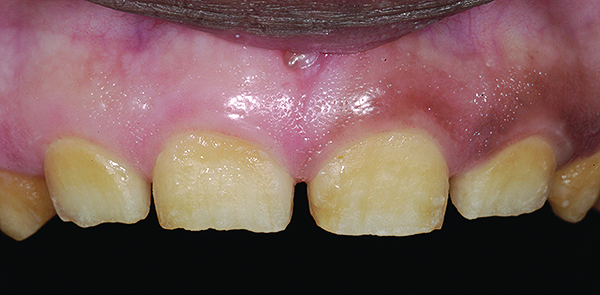

Figure 5. Preoperative 1:1 retracted frontal view.

Figure 5

The authors report on a 21-year-old patient who presented with severe discoloration and mild sensitivity of teeth (Figure 1). The teeth visible in his smile were very short, unsightly, and unbecoming for his age.

A thorough clinical examination and analysis were carried out to assess the esthetic and functional problems of the patient (Figure 2 through Figure 7). The medical history was non-contributory, except for mild leukoderma. Temporomandibular joint (TMJ) function was within normal range.

Mounted study casts were used to evaluate occlusion. The relevant findings were as follows2: Facial analysis revealed a canted maxillary occlusal plane and canted dental midline. Dentolabial analysis showed that the maxillary incisors were not adequately visible during repose; it also revealed a reverse smile line, as well as a wide smile showing 12 teeth. Results from the phonetic analysis were that “F” and “V” sounds revealed upper incisal shortening, “M” and “S” pronunciation disclosed a diminished vertical dimension of occlusion (VDO), and “E” sounds showed severe shortening of incisors. Dental analysis revealed thick biotype, asymmetry and inappropriate location of gingival levels and zenith, incorrect axial inclinations, a displeasing width-to-length ratio, and pitted surfaces on most teeth. Interproximal decay was evident on several posterior teeth, as revealed by radiographic analysis. Finally, occlusal examination indicated discrepancy between maximum intercuspation (MIP) and centric relation (CR) as well as a lack of anterior guidance/posterior disclusion.